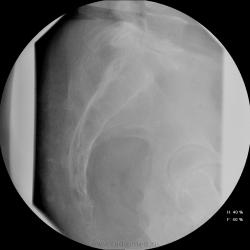

Женщина 55 лет, полная, поступила в неврологическое отделение с жалобами на боли в т.бедренных суставах,  области паха, больше слева. Лечили в поликлинике ДОА, остеохондроз- без эффекта, и направлили в стационар.

Остеохондроз от нижнегрудных позвоночно-двигательных сегментов и ниже, резко выраженный на уровне L5-S1 (3 степень снижения диска). Неполная люмбализация S1 - видны псевдосуставные щели на уровне боковых масс. Аномалия тропизма L5-S1: разноплоскостная ориентация щелей межпозвоночных суставов, один ближе к горизонтальной, второй - ближе к кософронтальной. Гиполордоз. Сколиоз. Деформирующий спондилез. Коксартроз 1 ст. с оссификацией крыш впадин. Флеболит(?!) в малом тазу слева, исключить конкремент в тазавой части левого мочеточника (ОАМ и т.д.; главное - экскреторная урография, желательно с прицельной РГ области мочевого пузыря в левой косой проекции на минуте 15-25).

Ну раз мнений больше нет - Мы заподозрили деструкцию в области тела подвздошной кости над вертлужной впадиной слева и отправили на КТ (обратите внимание на разряжение костной структуры по сравнению с правой стороной). На КТ : множественные очаги деструкции позвонков , больше пострадал остистый отросток L4. Такие же очаги в тазовых костях, наиболее крупный как раз слева над вертлужной впадиной. Левая половина крестца почти полностью разрушена. Кроме этого, очаги в печени, надпочечниках. Тело матки увеличено, в области придатков слева - кистозное образование. После этого посмотрели на наши сникми - почти сразу все увидели, особенно пропажу остистого отростка L4.

Имеем мтс, нужно теперь найти первичный очаг...